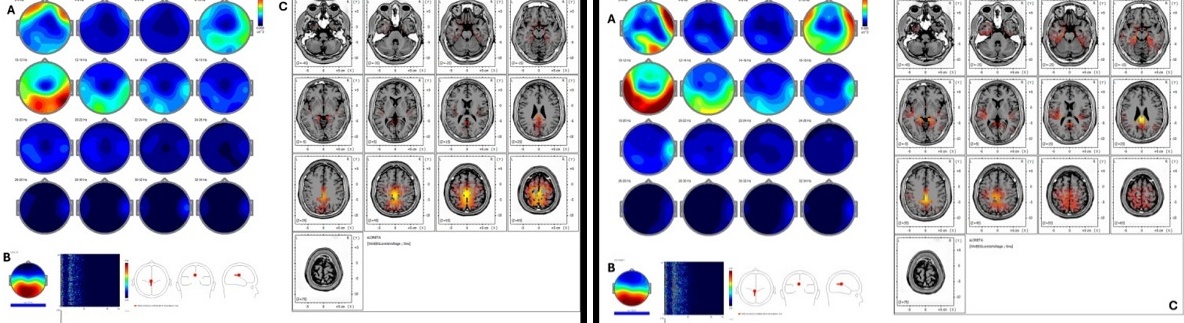

Se trata de un trabajo retrospectivo que incluyó a cinco individuos con exposición prolongada a estrés laboral y que evaluó la actividad cortical antes y después de 18 sesiones de REAC BWO-G utilizando métodos avanzados de análisis neurofisiológico (qEEG, ICA y sLORETA).

A la izquierda de la imagen, antes del tratamiento REAC / a la derecha, después del tratamiento

• Tendencias consistentes de aumento de simetría en bandas clave de EEG (delta, theta y alfa) y reorganización de la actividad cortical hacia redes asociadas con regulación emocional y cognición.

• Mejoras clínicas reportadas en estabilidad emocional, calidad del sueño y claridad cognitiva tras el tratamiento.

• Evidencia de que estas modificaciones neurofisiológicas se corresponden con patrones previos asociados a resiliencia frente al estrés.